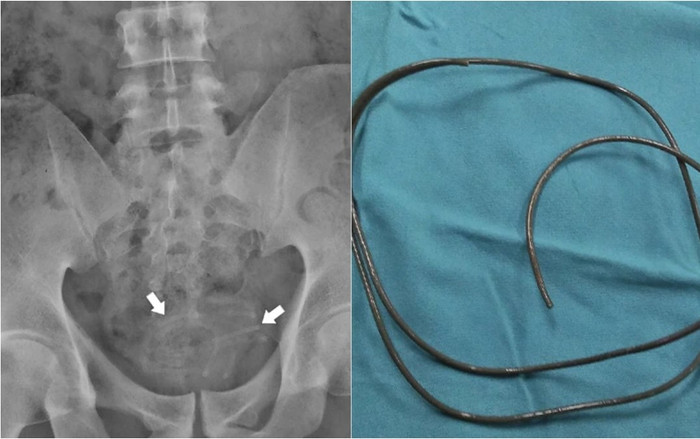

Chụp X-quang vùng chậu cho thấy một bóng mờ hóa ra là một sợi dây.

Theo các bác sĩ, sợi dây được cuộn lại và may mắn là không dính vào thành bàng quang, và việc lấy ra được thực hiện bằng kẹp nắm.

Dây tai nghe được phát hiện dày 2-3mm và chiều dài 80cm.

Bệnh nhân đã nhét dây tai nghe chiều dài 80 cm và đường kính 2-3 mm vào niệu đạo lúc 'tự sướng'.